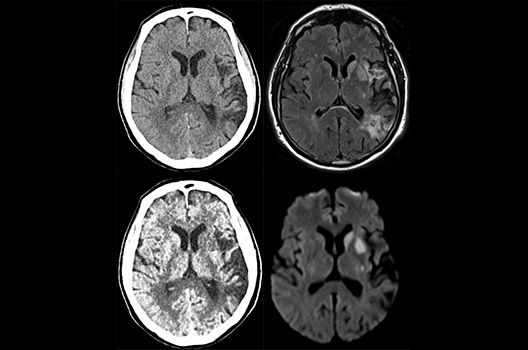

Die Schwerpunkte in der CT-Forschung liegen in der Bildnachverarbeitung, der Dosis- und Artefaktreduktion sowie der quantitativen und automatisierten CT-Bildanalyse.

Die Computertomographie (CT) ist ein Verfahren, bei der mit Hilfe von Röntgenstrahlung Schnittbilder des Körperinneren angefertigt werden. Unser Bestreben ist es hierbei, bei möglichst niedriger Strahlendosis eine bestmögliche Bildqualität zu erzielen. Eine zunehmend große Rolle in der radiologischen Forschung spielen zudem die Automatisierung in der Bildanalyse und die computergestützte Auswertung großer Datenmengen, wie sie bei einer CT-Untersuchung anfallen. Wir arbeiten in enger Kooperation mit den Geräteherstellern zusammen und sind daher maßgeblich an der Entwicklung und Erprobung neuer Techniken beteiligt.